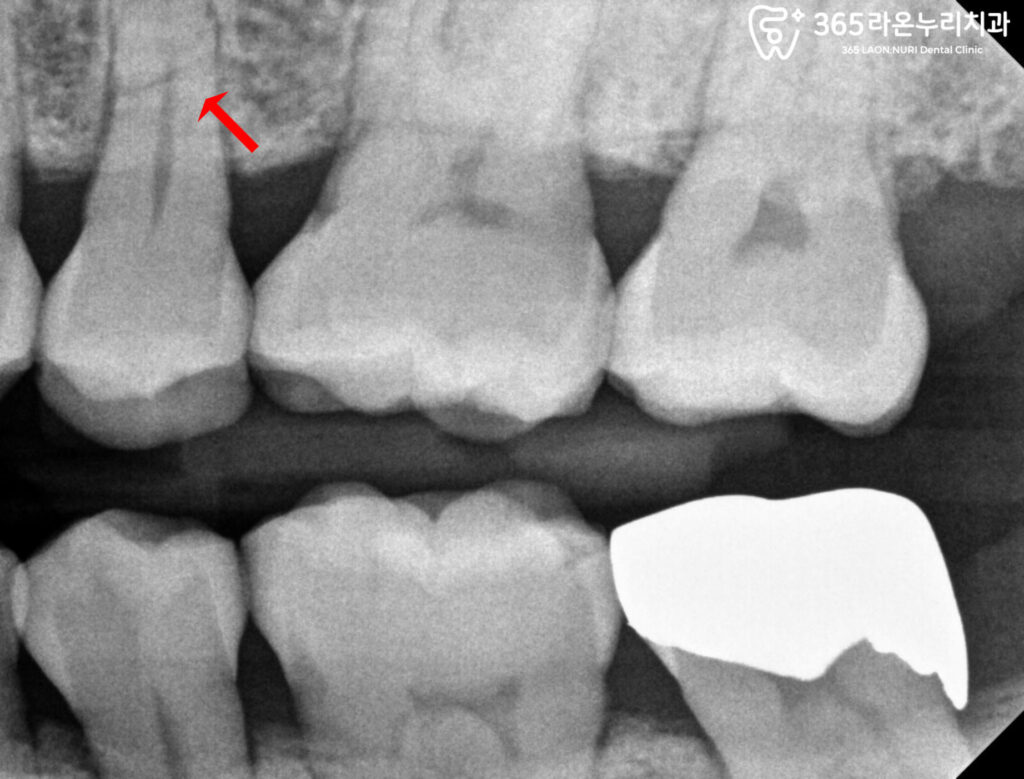

초진 엑스레이

촬영된 엑스레이를 보니

16번과 25번에 문제가 있는 것을

확인할 수 있습니다.

위 구강 내 사진을 보면 알 수 있듯

16번은 까맣게 우식이 관찰되며

25번은 치근이 파절된 것을 알 수 있습니다.